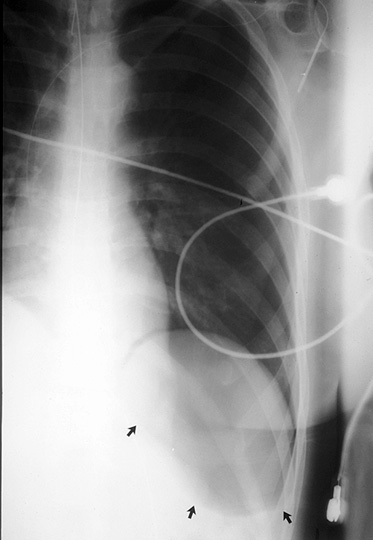

Gallery Blunt Chest Trauma Pneumothorax 1 deep sulcus

1 deep sulcus